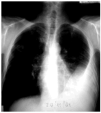

Fig. 1. Radiografía de tórax inicial con derrame pleural izquierdo e imágenes nodulares bilaterales.